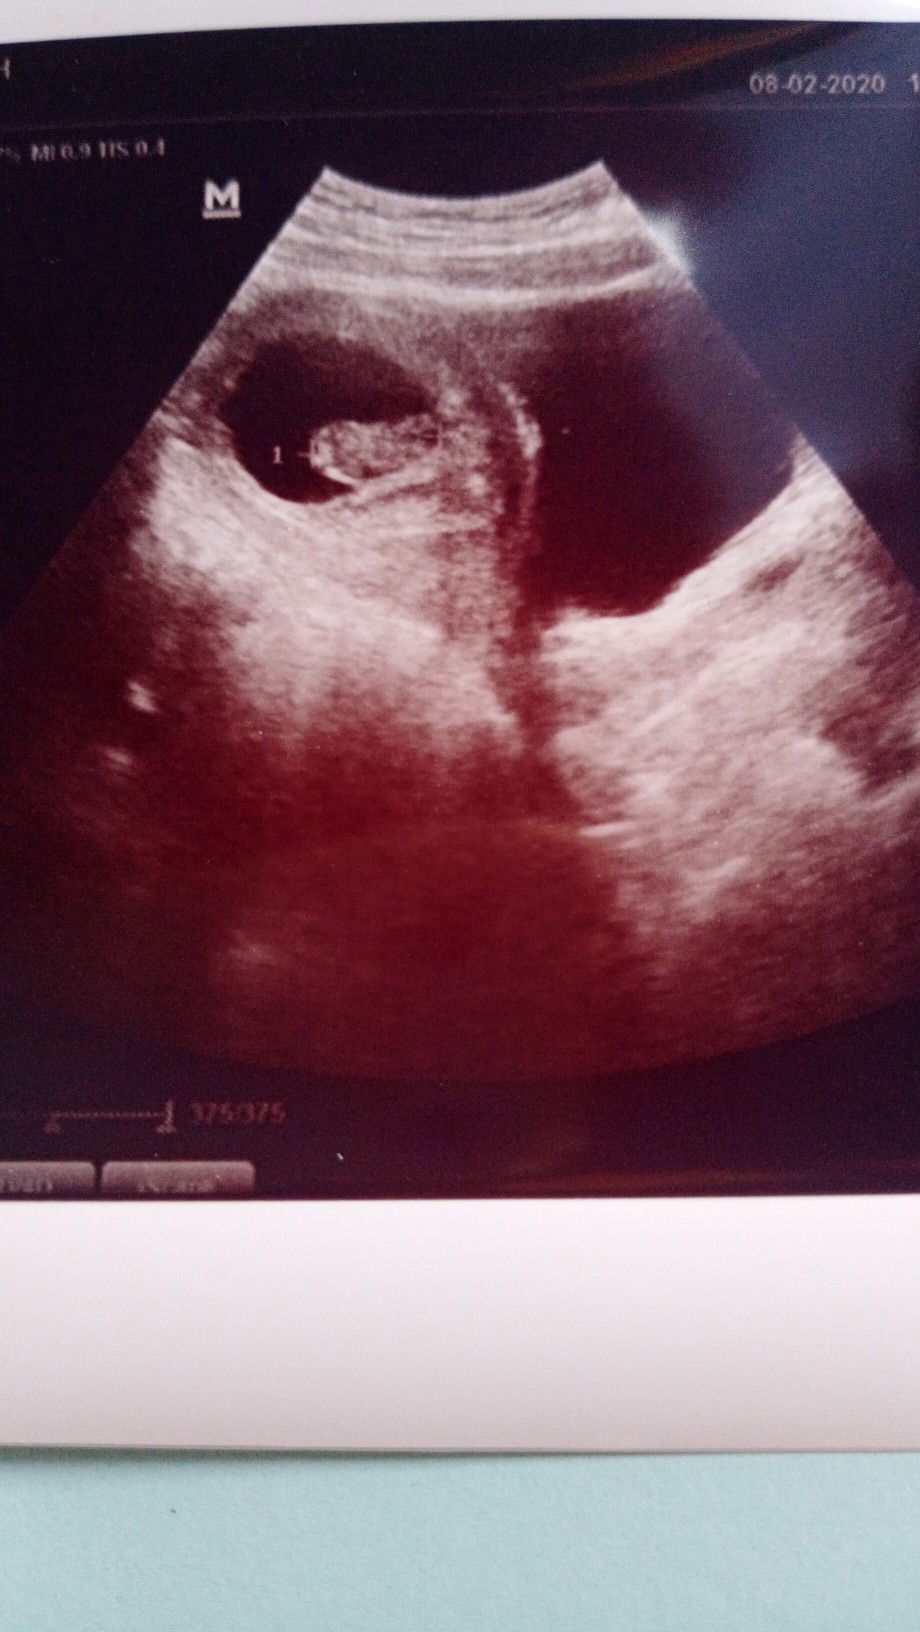

Usia 9 minggu

Iyah bun sama klau aku 9w3d 😇 jadi baru 2 bulan lbih